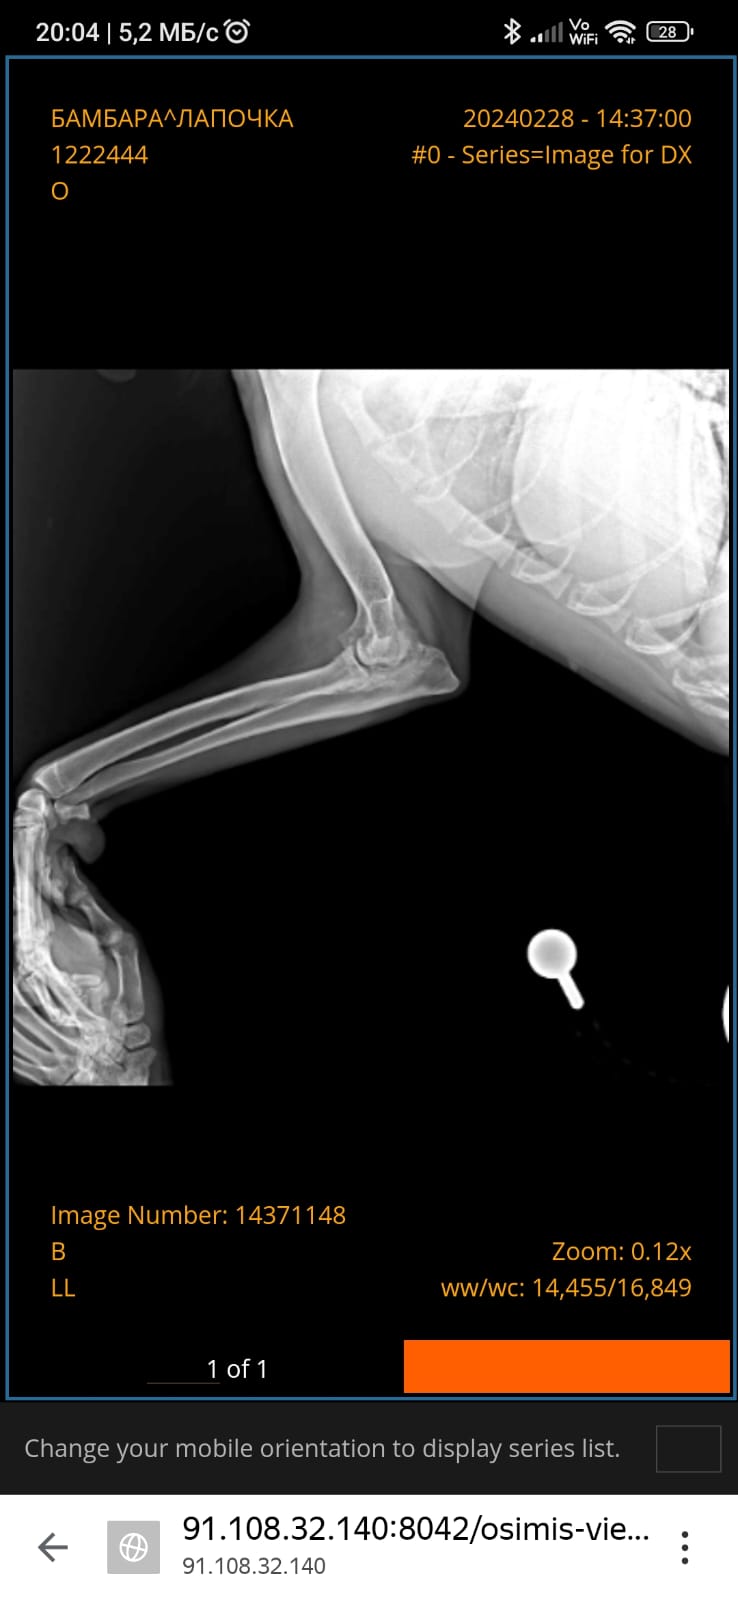

Локоть - левая передняя конечность

По сути вопроса.

Активный быстро растущий щенок, без ограничений по движениям, возможно на скользком полу....

Это привело к обострению воспаления в травмированном локтевом суставе, переносе центра тяжести на задние ноги....

Как следствие развитие дисплазии ТБС и в 11 месяцев разрыв передней крестовой связки коленного сустава левой тазовой конечности. ( Со стороны травмированного локтя).

Но проблемой левого локтевого сустава почему то не стали заниматься....

Соответственно, процесс имеет дальнейшее развитие.